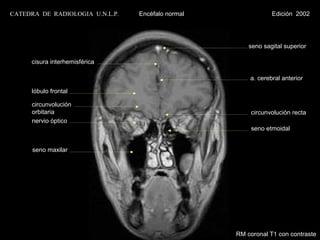

CATEDRA DE RADIOLOGIA U.N.L.P.   Encéfalo normal               Edición 2002

seno sagital superior

cisura interhemisférica

a. cerebral anterior

lóbulo frontal

circunvolución

orbitaria                                         circunvolución recta

nervio óptico

seno etmoidal

seno maxilar

RM coronal T1 con contraste